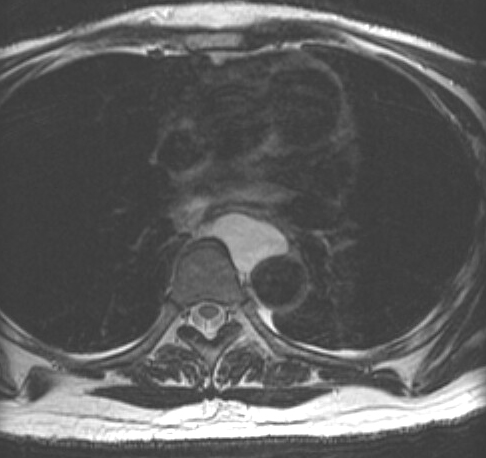

Bronch Cyst 2 MR